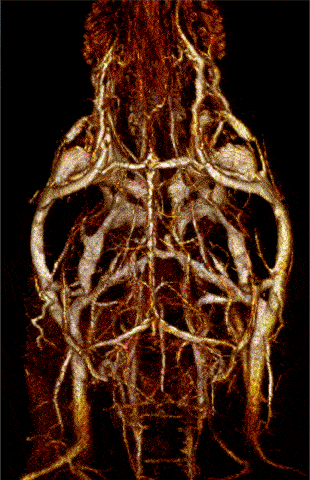

MR angiography with high T1 relaxivity liposomal-Gd contrast agents produces reconstructed 3D map of the cerebral vasculature of a mouse brain. Image Credit: Scintica Instrumentation Inc